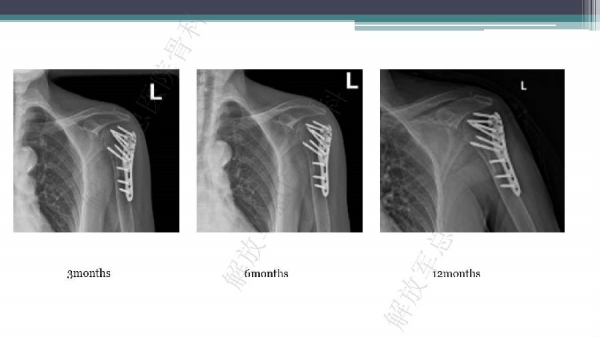

导 语:肱骨近端骨折仍是最常见的骨科损伤之一,尤其好发于老年人群。移位型肱骨近端骨折通常需要手术治疗,但是由于骨折粉碎、骨质较差,手术治疗往往会比较困难。随着锁定钢板的发明,使得并发症显著降低。但仍存在一些问题,对于内侧皮质不连续缺乏内侧可靠支撑,合并老年骨质疏松的病人,锁定钢板吊臂样结构就无法满足力学要求,随着康复锻炼可能出现断板、断钉、螺钉切出肱骨头等并发症。本期解放军总医院骨科专家们对老年肱骨近端骨折的问题与创新手术技术进行了详细讲解。